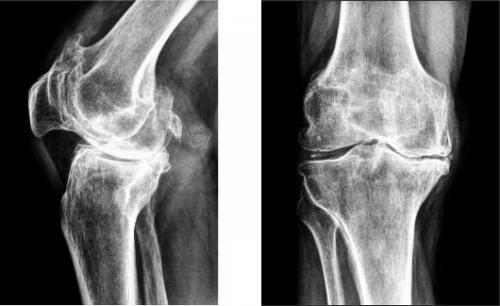

Стадии артроза коленного сустава. Обратите внимание на сужение суставной щели.

- гонартроз . Он встречается практически в 50% всех случаев поражения сочленения. Патология развивается очень долго. Среди симптомов этой болезни можно выделить такие: колено не болит в состоянии покоя, однако человеку становится трудно, долго ходить,. Во время движения больной слышит, у него снижается подвижность. Со временем, вследствие изнашивания хряща, расстояние между костными поверхностями уменьшается. При этом появляются, нервы и сосуды сдавливаются, а само колено деформируется;

В результате негативных процессов начинается процесс расслоения и истончения хрящевой ткани, что приводит к затруднению скольжения костей друг о друга. Кости расплющиваются, появляются костные разрастания, наблюдается уменьшение костной щели, что сопровождается постоянной болью и значительным снижением подвижности.

Ткань хряща нетрудно травмировать по причине слабого связочного аппарата, удерживающего сустав в нужном положении. Если хрящ утрачивает прочность и гладкость поверхности, истончается, суставы трутся, что приводит к усилению разрушения. Если процесс не остановить, могут образоваться костные выросты, которые называются остеофитами. Способствует разрушению и дефицит синовиальной жидкости.

На изображении справа заметно сращение суставной щели.